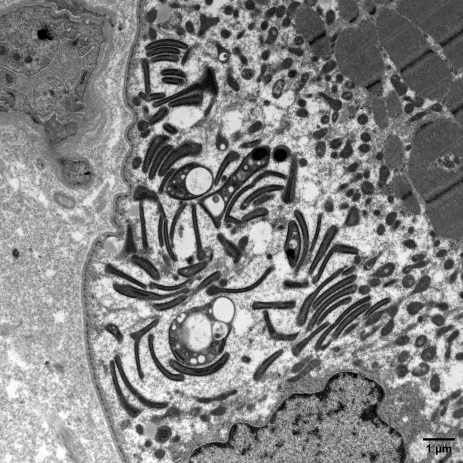

Micrographie électronique montrant des mitochondries anormales